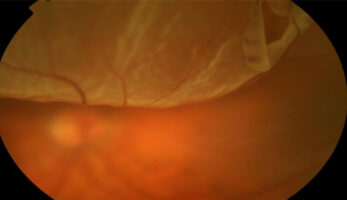

A serious eye condition where the retina separates from the back of the eye, requiring urgent treatment to save vision.